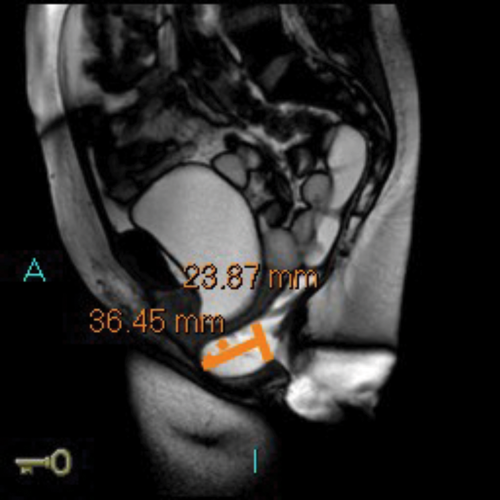

In addition the anterior and middle compartment is assessed, particularly for the presence and anatomy of a cystocoele or vault prolapse. The T2 sequences also allow pelvic evaluation for other incidental pathologies (Figure 2).

Figure 2c: Large cystocoele MR proctogram.

Figure 2d: Large rectocoele on MR proctogram.